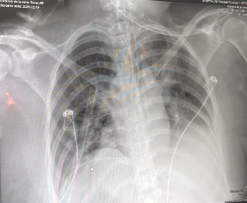

The patient was a 32-year-old female, who presented a cranioencephalic trauma and brain death confirmed by cerebral angiotomography. Her blood type was O with Rh positive and non-reactive viral panel, being compatible for the recipient. Physical examination revealed no abnormalities, it was not until a chest X-ray was performed as part of the pre-surgical protocol, where dextrocardia was not clearly identified due to poor technique, it was decided that based on the rest of the normal initial approach, she was a good candidate for donor.

Figure 3: (a) Dextrocardia is shown, with the tip of the heart to the right; (b) The inferior vena cava (2), which was to the left of the vertebral column and the common iliac artery (1) to the right of the vertebral column. View Figure 3

Figure 4: A chest X-ray is presented, with the cardiac silhouette with a tendency of cardiac apex to the right, without well delimiting the hepatic silhouette and the gastric bubble due to poor technique. View Figure 4